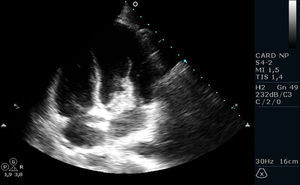

No 2.° dia de internamento, após deteção de sopro sistólico 2/6 no bordo esternal esquerdo, e em contexto de síndrome febril, foi realizado ecocardiograma transtorácico, que revelou válvula mitral com vegetação aderente à face auricular do folheto anterior, pediculada, hipermóvel, de grandes dimensões (30mm maior eixo), condicionando insuficiência mitral moderada a grave; PSAP estimada de 15mmHg (Figuras 1 e 2). Para melhor caracterização do mecanismo de insuficiência valvular e para exclusão de complicações perivalvulares, realizou ecocardiograma transesofágico, que confirmou a presença de vegetação volumosa, bem como insuficiência mitral grave, por interferência da vegetação na coaptação dos folhetos valvulares e excluiu abcesso, fístula, pseudoaneurisma ou perfuração.